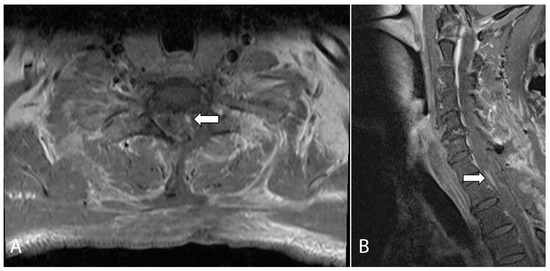

The patient subsequently underwent C7/T1 hemilaminectomy and excision of the T1 spinal cord lesion and left T1 nerve root. It was noted intraoperatively that there was a hard grayish tumor that was infiltrating along the left T1 nerve root and dorsal column of the spinal cord with both intra- and extramedullary components. Intraoperative frozen sectioning confirmed the presence of a spinal cord and nerve root neoplasm containing spindle and epithelioid cells. MRI performed on the first post-operative day demonstrated a small nodular enhancing focus, which raised the suspicion of residual tumor (Figure 2).

Figure 2.

Axial (A) and sagittal (B) T1-weighted, fat-suppressed, contrast-enhanced MRI of the cervical spine performed on post-operative day one. The images show a small nodular enhancing focus which raised the suspicion of a small focus of residual tumor (arrows).